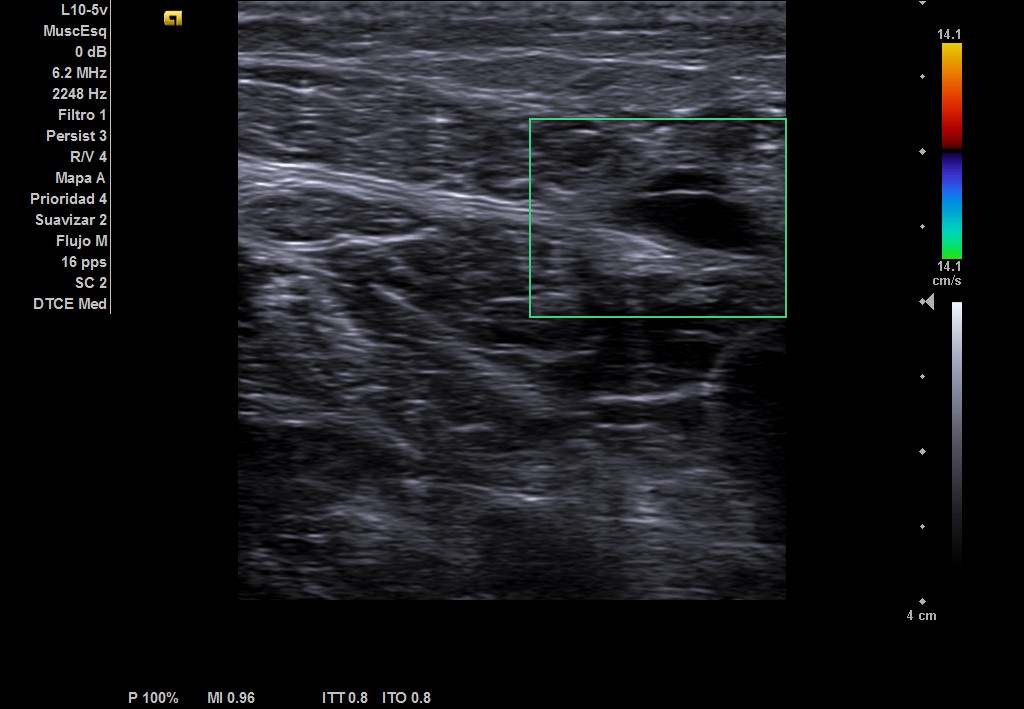

Ecografía musculoesqueletica: se objetiva signos de rotura de inserción gemeral interno-soleo de 21 x 32 mm y línea de líquido en zona superior intergastronemios de 1 mm de grosor. Doppler negativo.